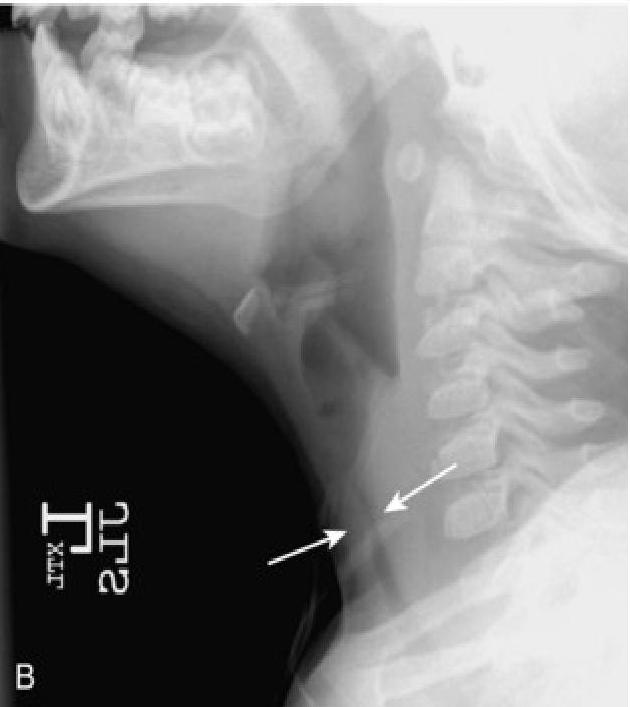

- The “Steeple Sign”: Characteristic subglottic narrowing seen on X-ray.

- X-ray, steeple sign